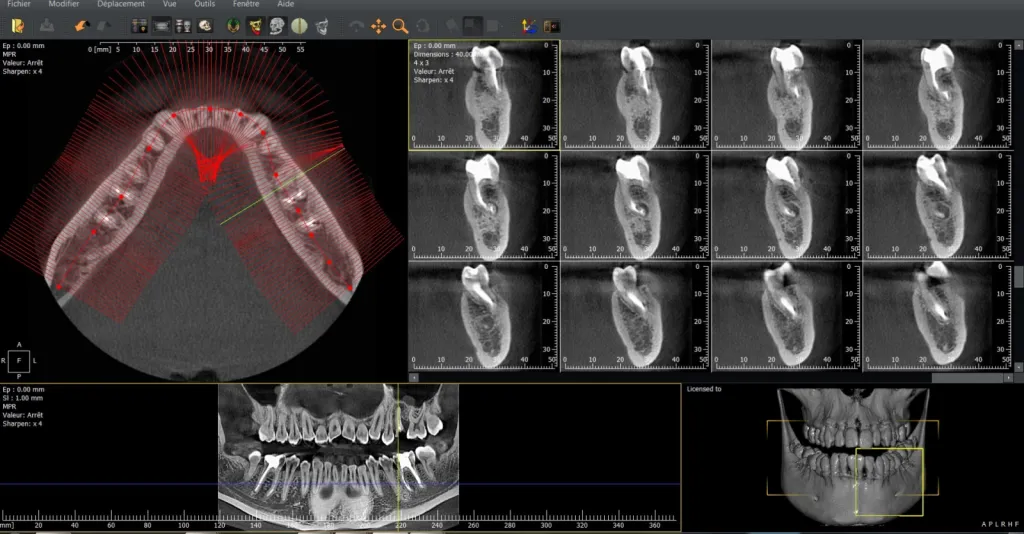

Radiologie volumique par faisceau conique CBCT : imagerie 3D précise, faible irradiation, référencée sous le code médical LAQK027.

La radiologie volumique par faisceau conique (CBCT) et le code LAQK027 La radiographie volumique par faisceau conique (CBCT) représente une évolution majeure dans le domaine de l’imagerie médicale et dentaire. Cette technologie fournit des images tridimensionnelles précises des structures anato...